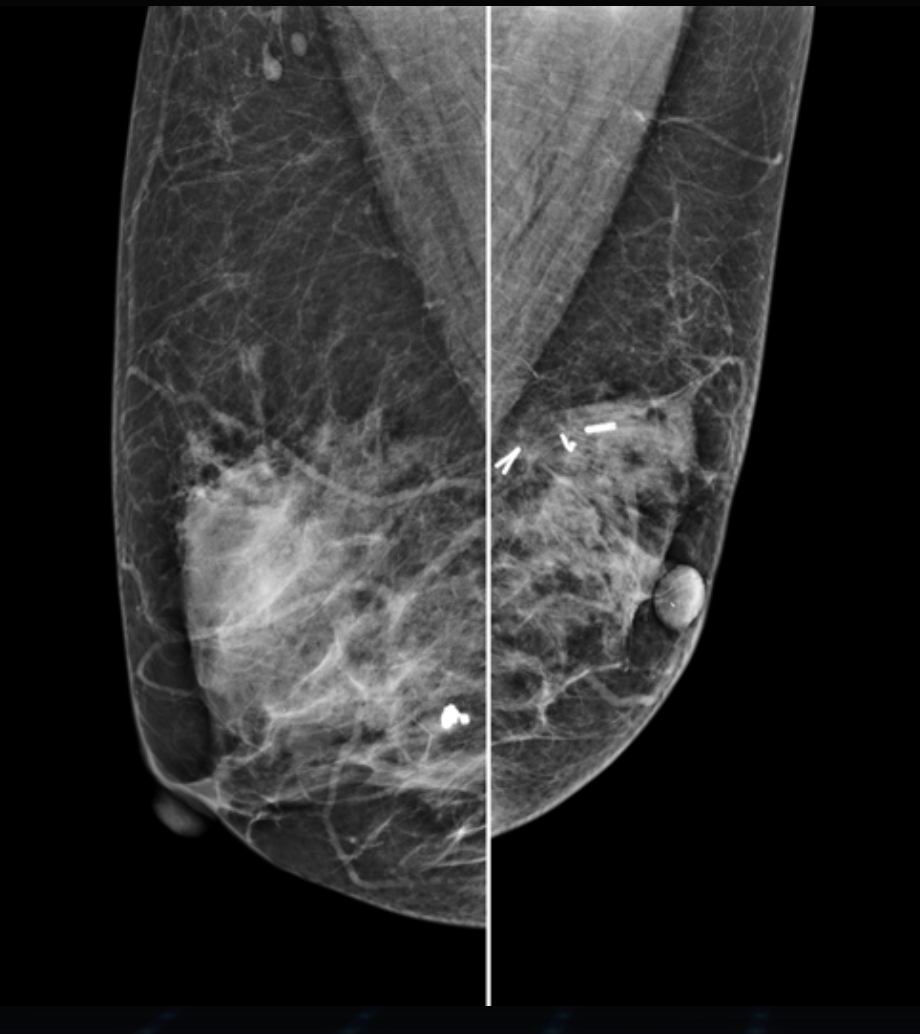

Tomosynteza 3D

Hestia została zaprojektowana jako system modułowy, który umożliwia rozbudowę o tomosyntezę piersi – warstwowe obrazowanie 3D, zwiększające wykrywalność zmian.